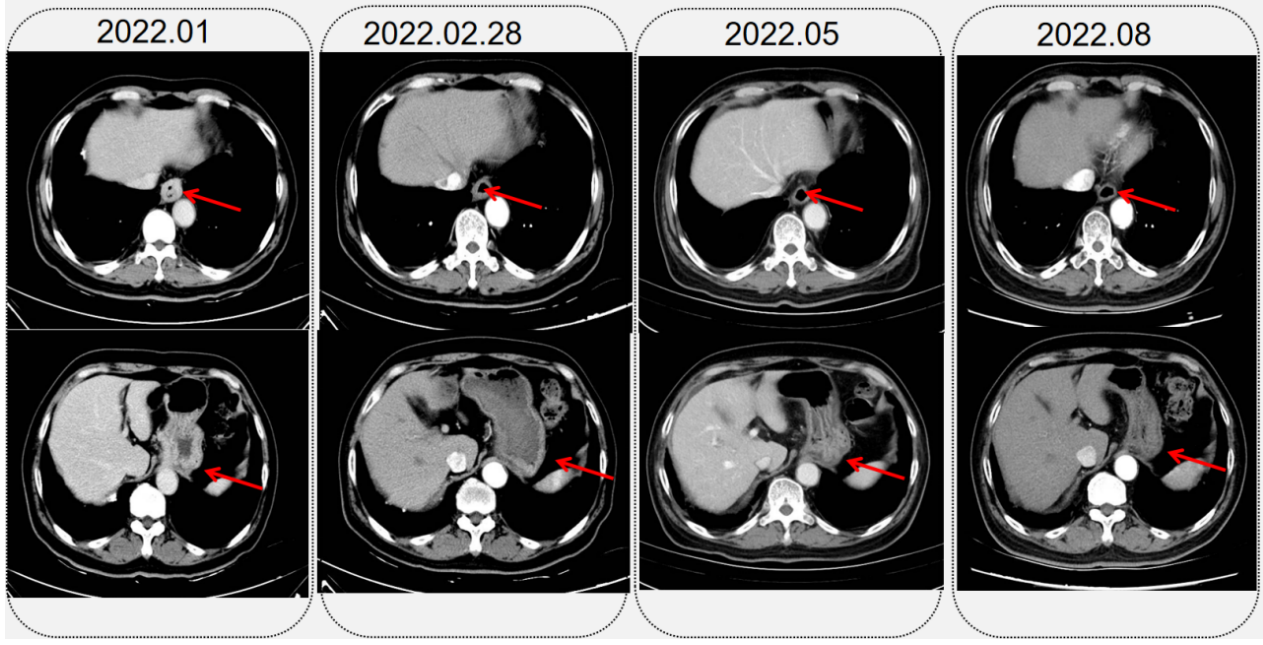

患者拒绝手术。为进一步治疗入肿瘤内科,行PD-L1检测:TPS=0,CPS=15。在我科行免疫联合化疗治疗,具体方案:替雷利珠单抗200mg+奥沙利铂200mg d1+卡培他滨1.5g d1-14,治疗过程顺利,治疗后进食哽噎感明显好转。免疫治疗联合化疗2周期后复查食管下段及贲门局部管壁不均匀增厚,较治疗前明显变薄,周围淋巴结较前减小,疗效评价:稳定(SD-)。

第3-5周期继续原方案治疗。第6周因手足反应较重,调整方案为替雷利珠单抗200mg+奥沙利铂200mg d1。其中于第4、6周期分别复查评估疗效。第4周期后CT显示食管下段进一步变薄。第6周期后复查,CT显示食管下段及贲门局部管壁治疗后改变,食管下段周围、胃小弯未见肿大淋巴结。PET/CT:食管MT治疗后病例:食管下段及局部贲门食管略厚,糖代谢正常,考虑治疗后改变;下段食管旁、胃小弯多发淋巴结影显示,伴轻度糖代谢,延迟显像轻度减低,考虑治疗后改变。复查胃镜:食管全程粘膜光滑,未见溃疡、糜烂;非萎缩性胃炎,十二指肠球炎。疗效评价CR。

2.png

1.png

2022年8月-2023年4月:单药替雷利珠单抗200mg q3w,维持治疗12周期,期间评效持续稳定。